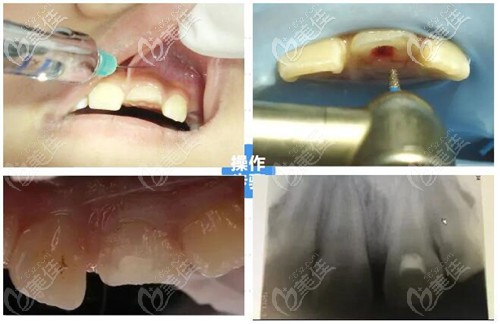

活髓切断术是在局部麻木的方式下将牙冠部位的牙髓切断并且去除,再用盖髓剂覆盖在牙髓断裂上,以此来保留健康的牙齿根髓。

根管治疗的方式和目的主要是清理牙齿根管内的牙髓炎症和坏死物质,通过适当消毒充填根管达到牙髓的治疗的效果,但主要是战队牙髓坏死不能保留活髓的情况下进行治疗。

活髓切断术和根管治疗都是牙髓病的治疗,两者的价格相差不大,我觉得楼主如果牙齿摔断得先判断牙髓是否活髓,如果活髓进行活髓切断术治疗,然后再用进行牙齿折断处的修补。如果牙髓坏死那就先进行根管治疗,然后再考虑做种植牙或烤瓷牙修复。

亲,做根管治疗还是活髓切断术得看你的牙髓情况。如果只是门牙折断但是牙髓健康,修复办法是活髓切断术+断冠再接术,对牙齿折断的部位保留健康牙髓,这样牙髓健康,牙齿才能更好地维持,手术价格一般在500元起。

如果牙髓感染、病变就做根管治疗,对牙齿炎症消除,治疗费用一般是300元起,一般需要2-4次治疗才能完成。我觉得这两个无论哪一个你得看医生技术,手术技术好两项都效果都不错,你参考下我的建议。